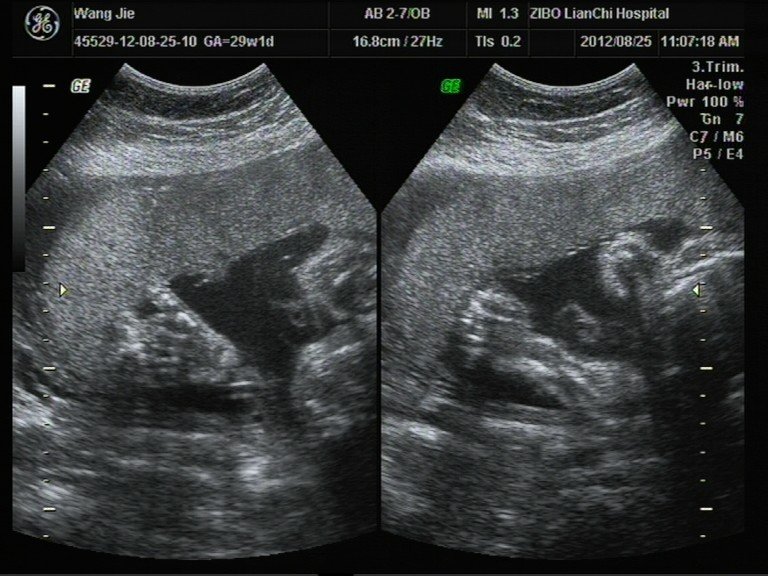

患者信息:女 29岁 病情描述(发病时间、主要症状等):彩超数据和相关照片,想知道宝宝男女。其余大部分照片在我百度空间的相册中。想得到怎样的帮助:想知道宝宝性别。曾经治疗情况及是否有过敏、遗传病史:四维彩超不清楚发哪张好。其余在我的百度空间中。

楼主,你的图像太模糊了,还是去找个认识的医生叫他帮你再看看吧。 四个半月